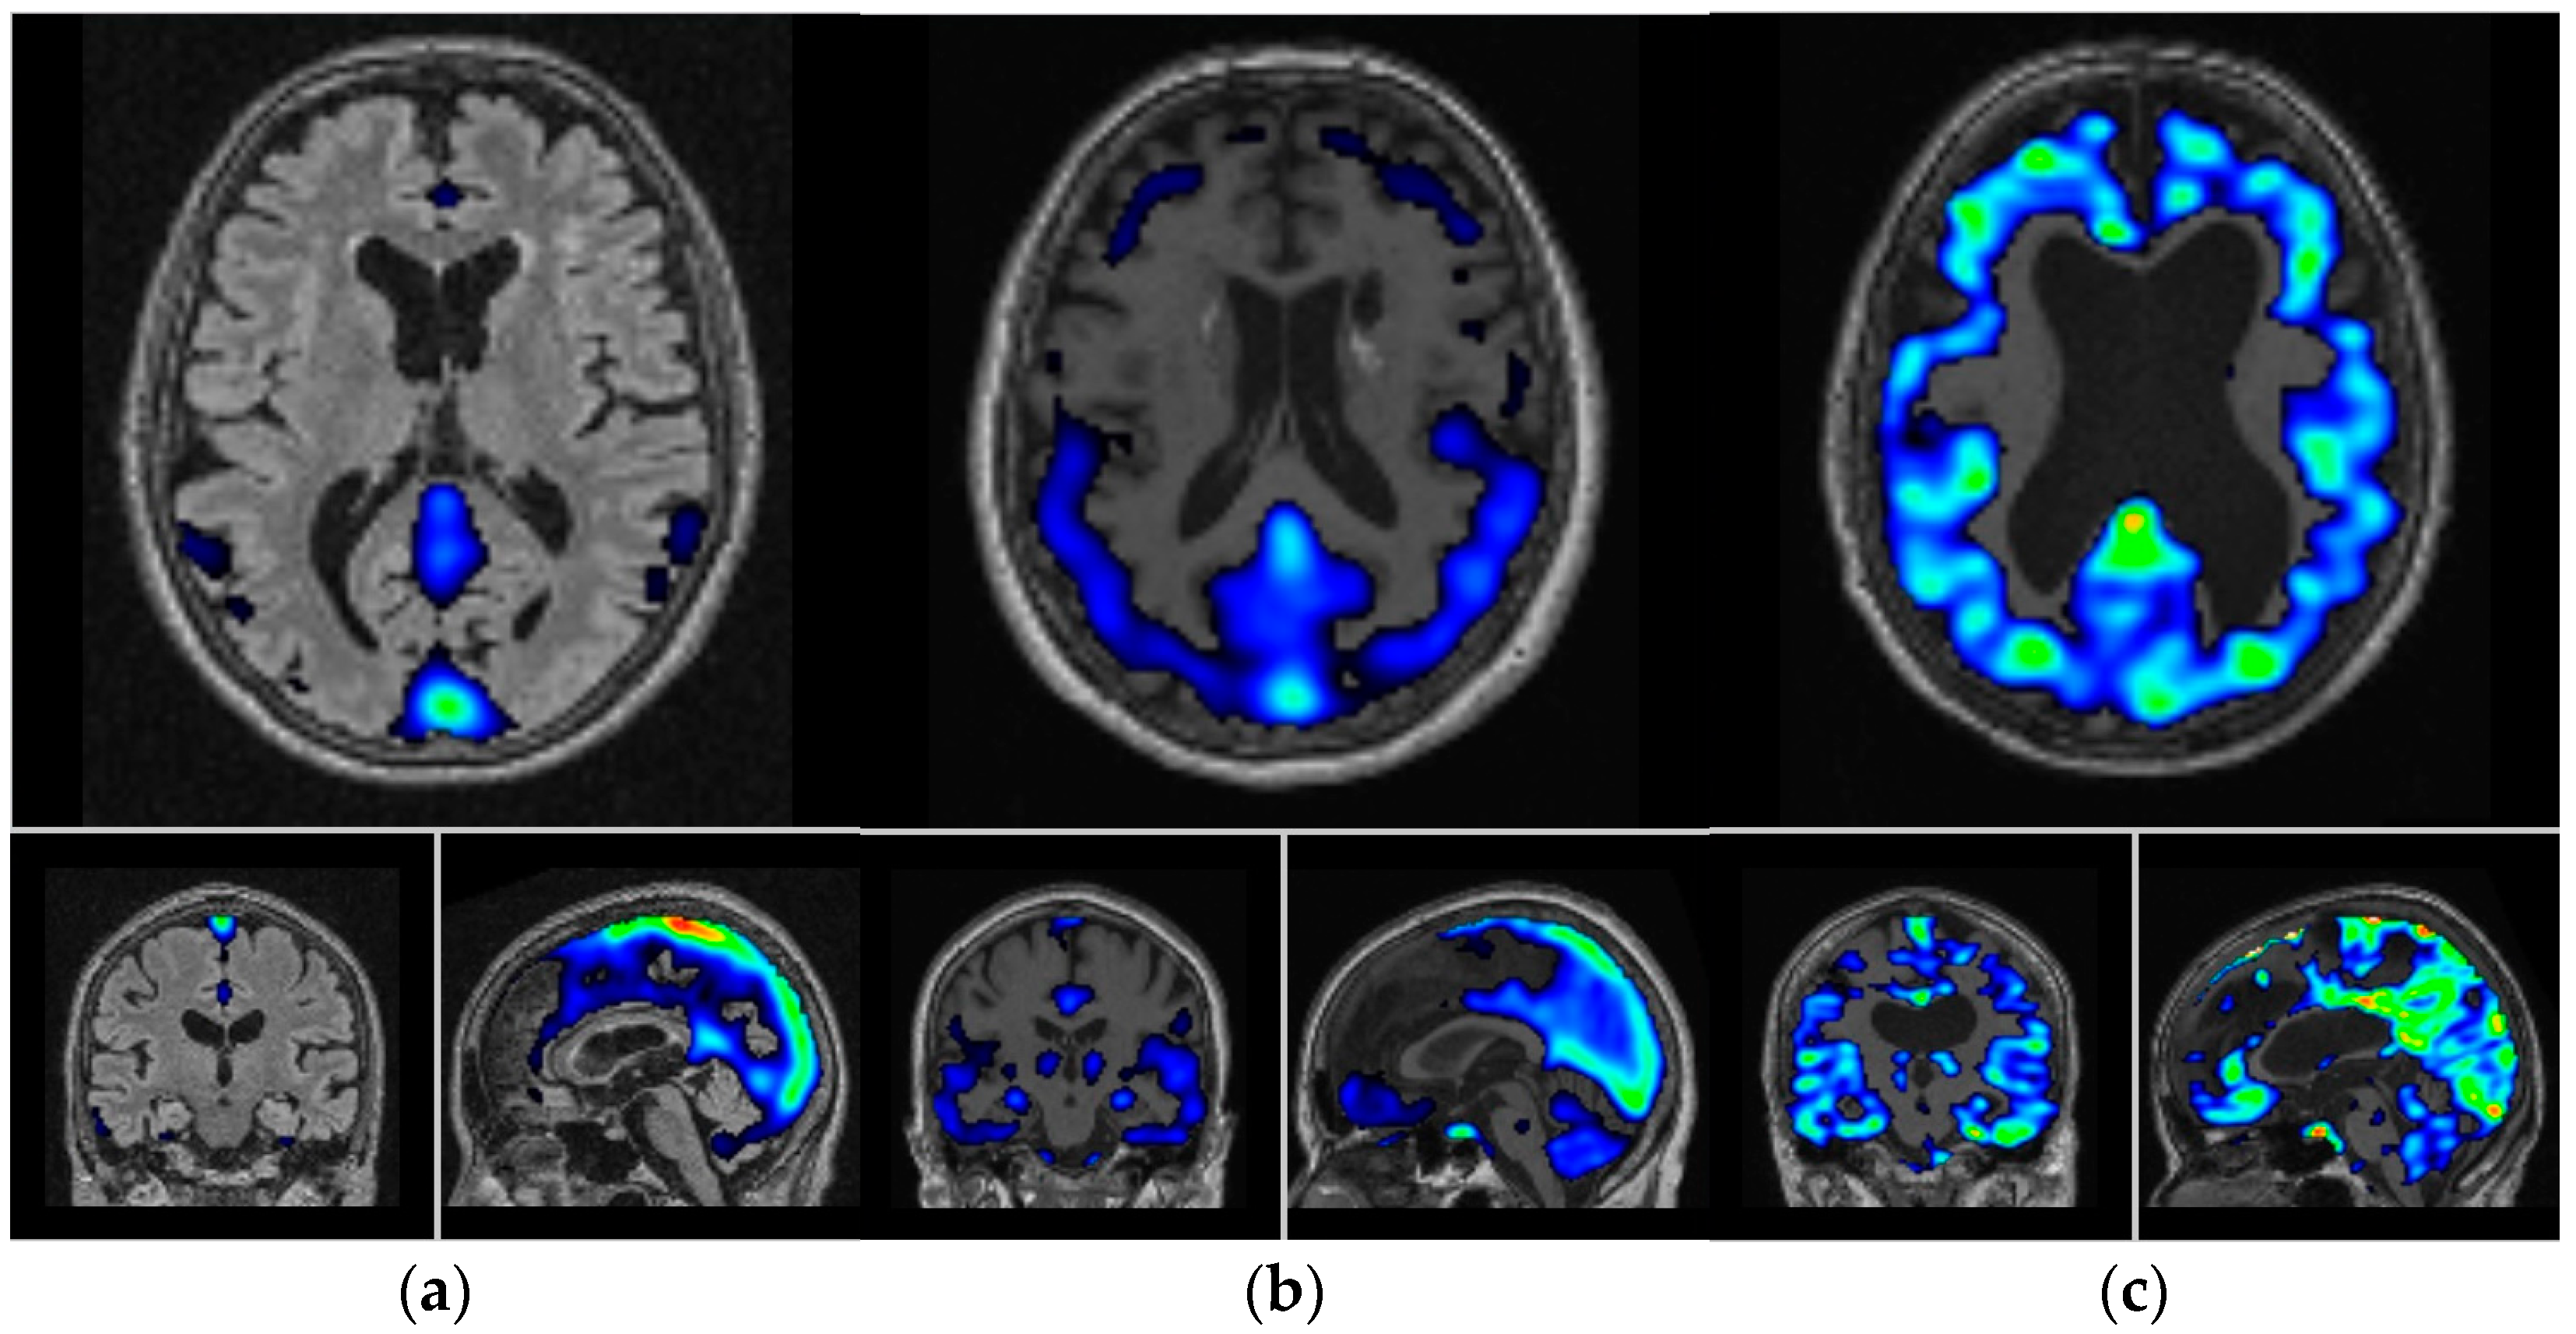

- Yousefzadeh-Nowshahr, E.; Winter, G.; Bohn, P.; Kneer, K.; von Arnim, C.A.F.; Otto, M.; Solbach, C.; Anderl-Straub, S.; Polivka, D.; Fissler, P.; et al. Comparison of MRI-based and PET-based image pre-processing for quantification of 11C-PBB3 uptake in human brain. Z. Fur Med. Phys. 2021, 31, 37–47. [Google Scholar] [CrossRef] [PubMed]

- Della Rosa, P.A.; Cerami, C.; Gallivanone, F.; Prestia, A.; Caroli, A.; Castiglioni, I.; Gilardi, M.C.; Frisoni, G.; Friston, K.; Ashburner, J.; et al. A standardized [18F]-FDG-PET template for spatial normalization in statistical parametric mapping of dementia. Neuroinformatics 2014, 12, 575–593. [Google Scholar] [CrossRef] [PubMed]

- Perani, D.; Della Rosa, P.A.; Cerami, C.; Gallivanone, F.; Fallanca, F.; Vanoli, E.G.; Panzacchi, A.; Nobili, F.; Pappata, S.; Marcone, A.; et al. Validation of an optimized SPM procedure for FDG-PET in dementia diagnosis in a clinical setting. Neuroimage Clin. 2014, 6, 445–454. [Google Scholar] [CrossRef] [PubMed]